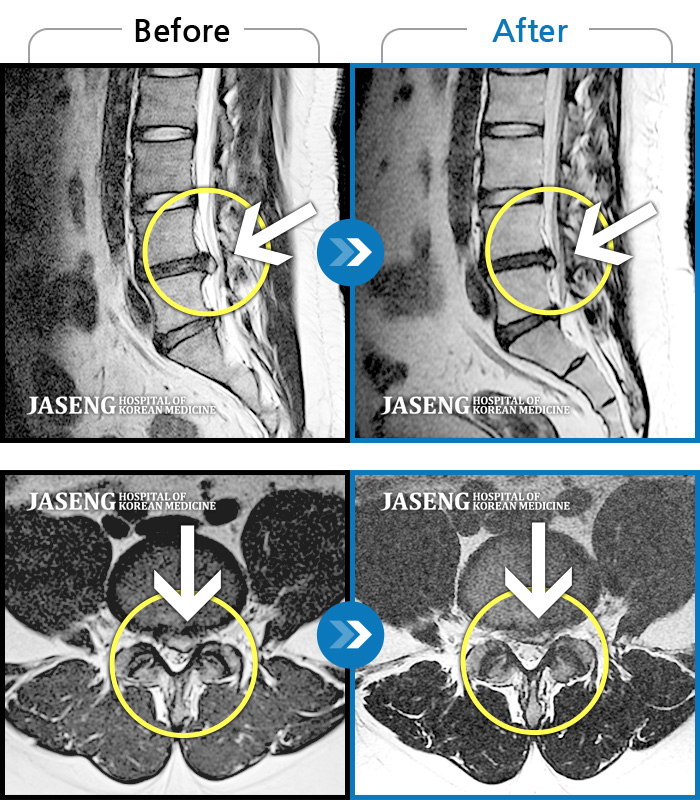

허리디스크

일산 · 김태용 원장

허리와 좌측 다리가 당겨 보행이 불가능했다.

촬영시기

2020.02.10 ~ 2021.02.22

2021.02.26

조회수 103